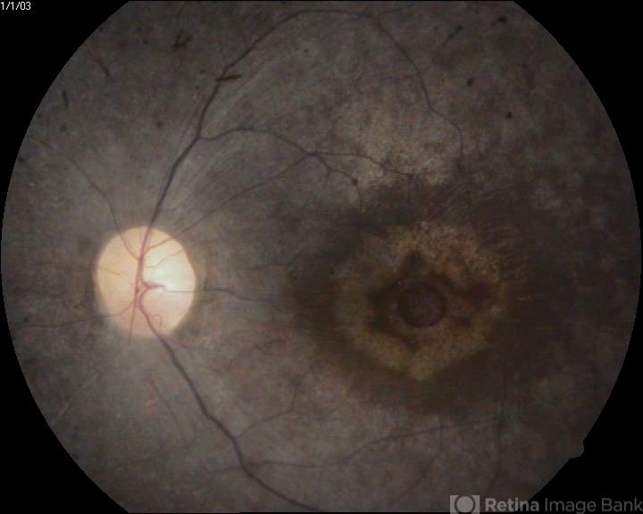

- bull's eye maculopathy

- A 45-year-old female presented with gradual reduction in vision.